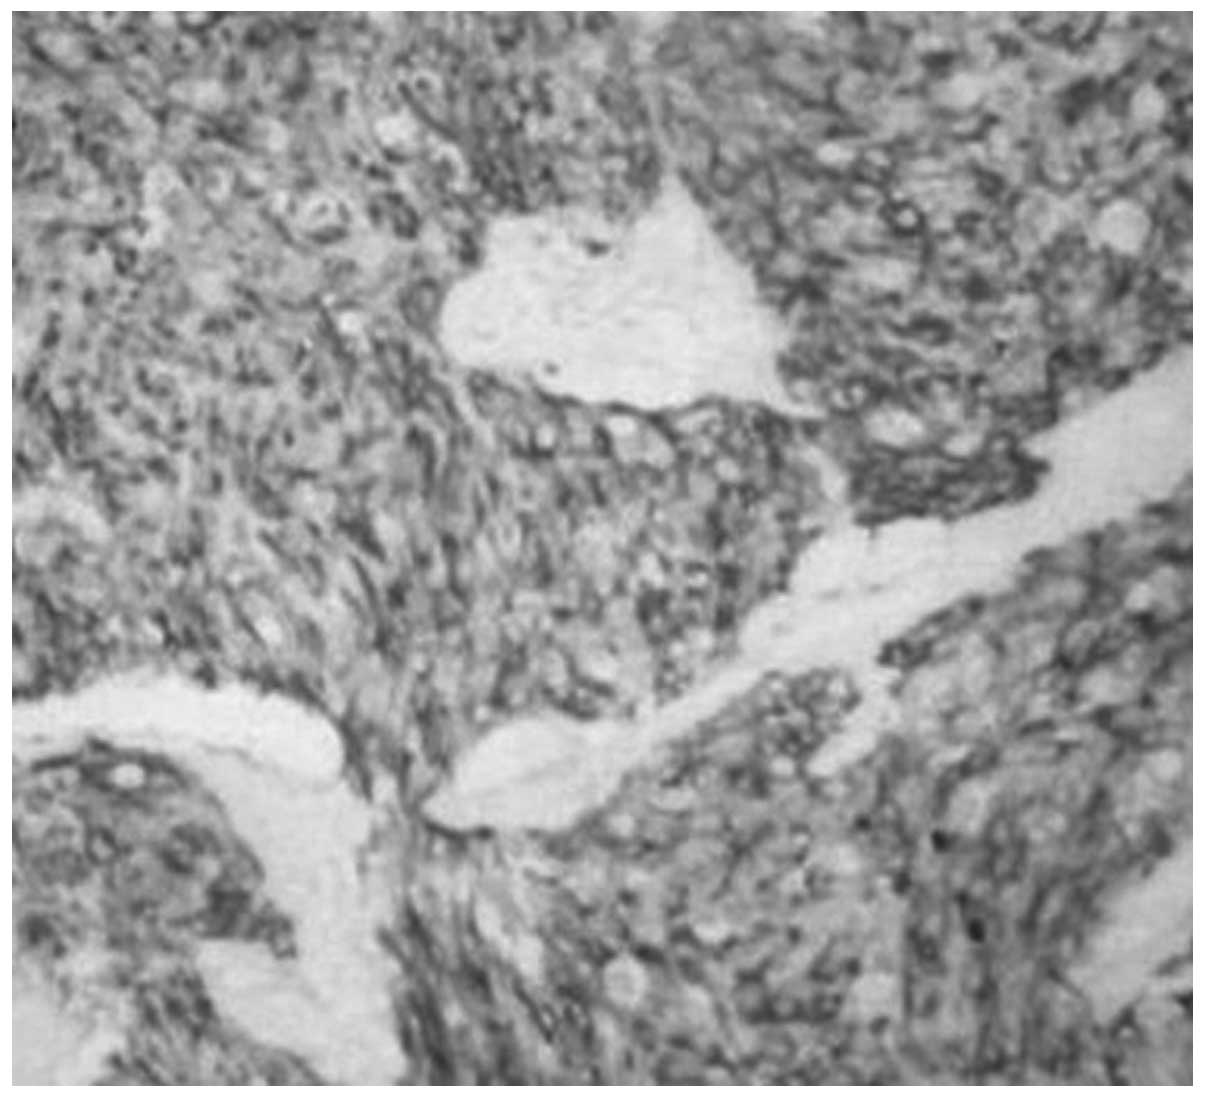

Primary desmoplastic small round cell tumor of the testis: A case report and review of the literature

Desmoplastic small round cell tumors (DSRCTs) are extremely rare and mainly affect adolescents and young adults. The tumors are usually involved with the abdominal area and/or the pelvic peritoneum. Only a small number of cases have been reported concerning DSRCTs of the testicular region. The present study reports a case of DSRCT of the testis with radical orchectomy and systemic chemotherapy, leaving the patient disease-free for 14 months. However, the patient died of multiple metastasis 12 months later. Furthermore there is a review of the English literature to analyze the incidence, site of origin, imaging and pathological characteristics of DSRCT.

Figure 4